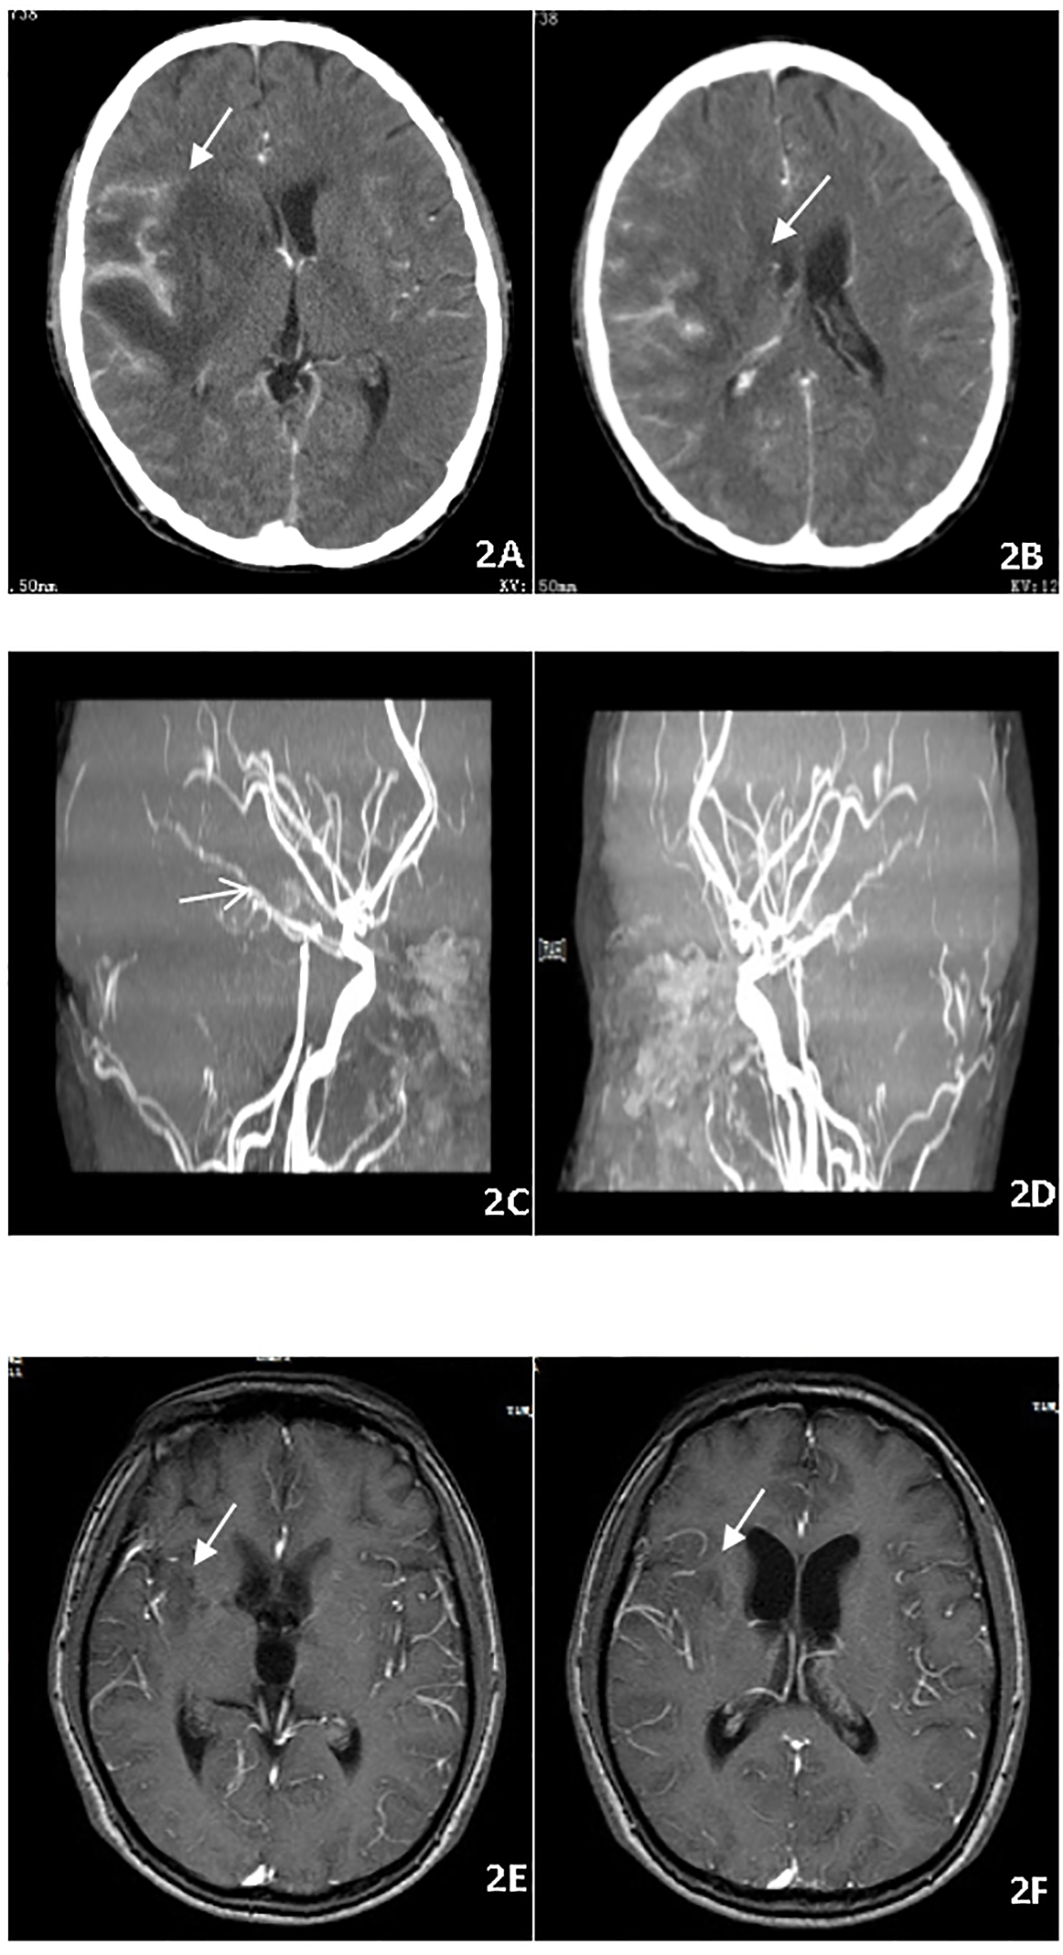

A 28-year-old male on treatment for pulmonary TB, pleurisy, and peritonitis for two weeks presented with fever, headache, vomiting, coma, and cough. Neurological examination revealed a dense right-sided hemiparesis in isolation and neck rigidity (Glasgow Coma Scale GCS 8/15). Brain CT imaging (Figures 2A–D) confirmed an abnormal signal in the right temporal lobe with associated meningeal thickening and enhancement, and multiple linear and nodular enhancement was observed in the area of the right middle cerebral artery. Hydrothorax was positive for X-pert MTB/RIF assay with no RR. The culture of sputum and hydrothorax was positive for MTB after three weeks. The patient commenced ATT and dexamethasone. After 16 weeks of therapy, the patient remained with right-sided hemiplegia evident on exercise and intellectual disability. The patient’s meningitis was complicated with vasculitis. So thalidomide was started at a dose of 3.3 mg/kg/d for two months to maximally inhibit inflammation. In the days following the initiation of thalidomide, the patient became more responsive and was able to follow simple one-stage commands and move his right limbs,and MRI showed obvious improvement of intracranial lesions (Figures 2E, F). After 18 months of ATT, the patient improved and was able to walk by himself with a mild limp. Computational power, cognitive ability and linguistic ability improved but did not reach the level of his peers.

Figure 2

(A–D) Brain CT imaging before treatment, abnormal signal in the right temporal lobe with meningeal thickening and enhancement and multiple linear and nodular enhancement in the right middle cerebral artery. (E, F) Brain MRI showed thalidomide treatment improved the intracranial lesions after 2 months.